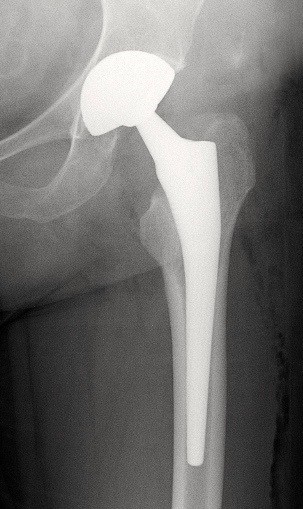

Prothèse totale de hanche sur arthrose

Cette intervention remplace une hanche usée par l’arthrose.

Supprimer la douleur et retrouver une mobilité confortable.

La reprise de la marche est rapide, souvent dès les premiers jours, avec aides à la marche transitoires.

Prothèse totale de hanche sur fracture

Indiquée principalement chez les personnes âgées après une fracture du col du fémur.

Permettre une remise en charge rapide et limiter les complications liées à l’alitement.

Encadrée par une équipe pluridisciplinaire, avec rééducation précoce.